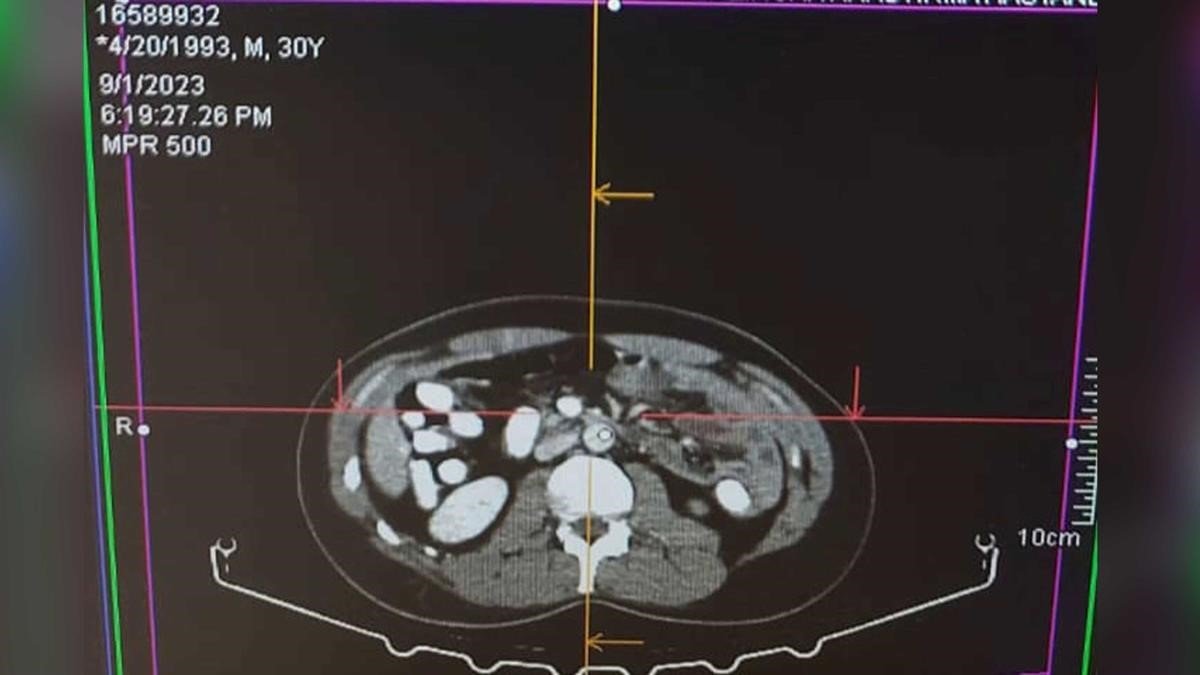

İl Emniyet Müdürlüğü Narkotik Suçlarla Mücadele Şube Müdürlüğü ile Kaçakçılık ve Organize Suçlarla Mücadele Şube Müdürlüğü ve İstihbarat Şube Müdürlüğü ekiplerince yapılan ortak çalışmada; Uygulama noktasında durdurulan, yolcu otobüsünde yolcu olarak bulunan A.A isimli şahsa alınan iç beden muayenesi kararına istinaden hekim gözetiminde çekilen "tomografi" neticesinde mide ve bağırsak kısmında uyuşturucu madde olabileceği değerlendirilen yabancı maddeler tespit edildi. Şahıs Mengücek Gazi Eğitim ve Araştırma Hastanesinde müşahede altına alınarak midesinden 70 adet kapsül halinde daralı ağırlığı ise 499,23 gr Afyon sakızı maddesi ele geçirildi.